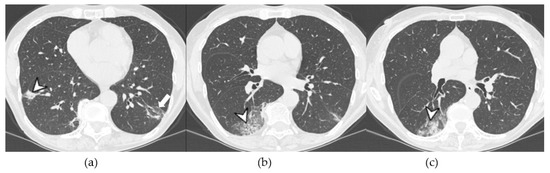

4.2.1. HRCT Findings of Patients with Anti-ARS Abs

- Waseda, Y.; Johkoh, T.; Egashira, R.; Sumikawa, H.; Saeki, K.; Watanabe, S.; Matsunuma, R.; Takato, H.; Ichikawa, Y.; Hamaguchi, Y.; et al. Antisynthetase syndrome: Pulmonary computed tomography findings of adult patients with antibodies to aminoacyl-tRNA synthetases. Eur. J. Radiol. 2016, 85, 1421–1426. [Google Scholar] [CrossRef]

| Lesions | GGO, reticulations, consolidations | consolidations, GGOs | |

| Distribution | Homogeneous; lower lung lobes, along bronchovascular bundles and lung periphery; loss of volume of lower lobes | Patchy; peripheral lower lobes or along the bronchovascular bundles | |

| CT pattern | NSIP OP NSIP-OP UIP DAD-unclassifiable | 50% 20% 25% 10% +/− | 20% 50% 25% <5% ++ |